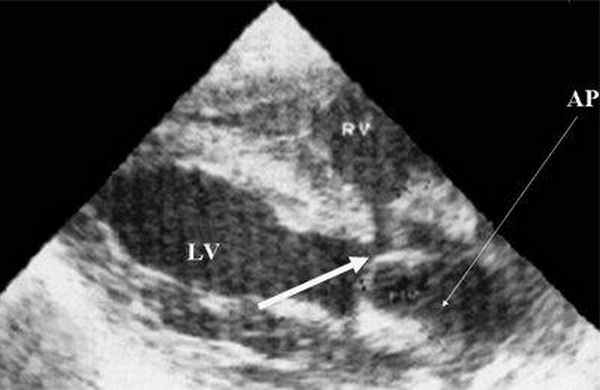

Трехмерно реконструированные перспективы у пациента с врожденной корригированной транспозицией, большим дефектом межжелудочковой перегородки (VSD) и рудиментарным правым желудочком (RV).

На кадре слева показано продольное сечение через левый желудочек (LV), из которого исходит отчетливо расширенная легочная артерия (РА); кроме того, здесь же фронтальный вид на расположенный в глубине VSD.

Рис. 1. Систолическая перегрузка правого желудочка. Поперечное сечение желудочков сердца при стенозе легочной артерии. Градиент давления правый желудочек - легочная артерия равен 200 мм рт.ст. Выраженная гипертрофия межжелудочковой перегородки и миокарда передней стенки правого желудочка.

Рис. 2. Длинная ось сердца. Объемная перегрузка правого желудочка при дефекте межпредсердной перегородки. Объем сброса крови превышает 200% МОС. Отмечается выраженная дилатация правого желудочка.